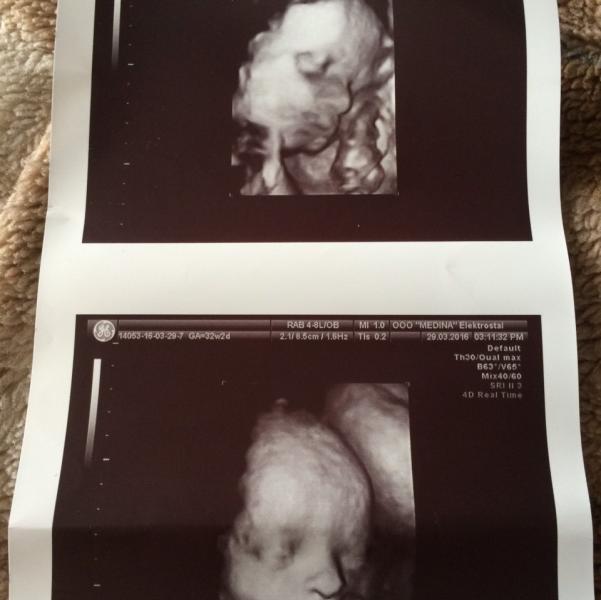

Это мы!наконец то знаем кто в домике живёт...мальчик...ещё один сынок...ещё один мамин защитник!)перевернулись мы из головного предлежания в тазовое,сказали что отстаём на две недели,назначали актовегин+куралтин и придти провериться через 10 дней!

@gavryusha, @rina_kisss да в Медине была час назад,это обычное узи третьего триместра,они сами там там делают зд что б посмотреть на малыша